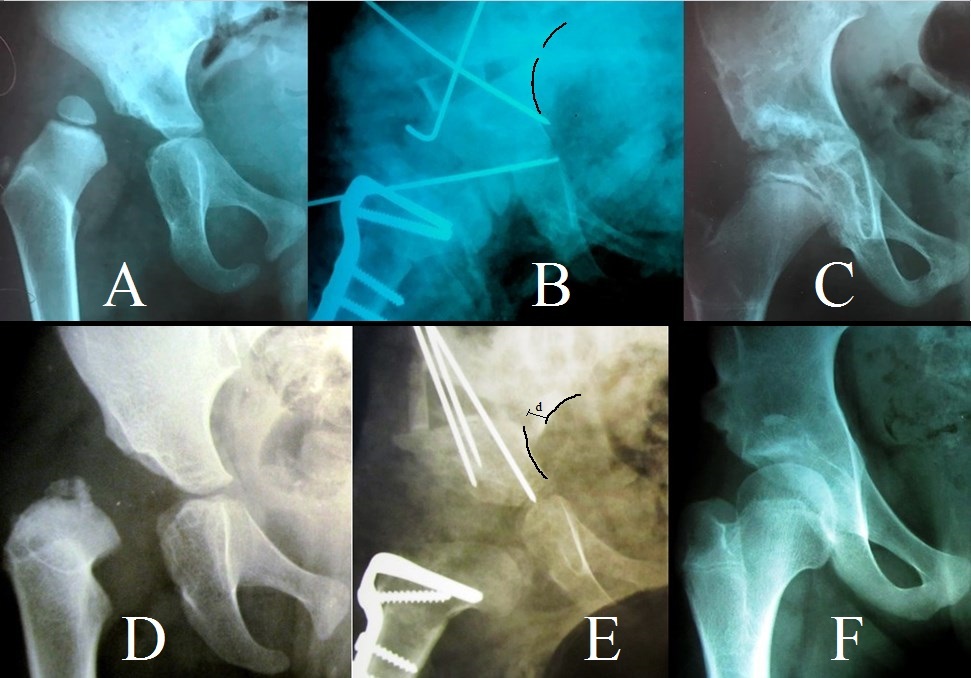

Determining risk factors that don’t depend on the surgeon’s skills we’ve found that patient age and acetabular deformity degree (preoperative AI value) affect clinical and radiological outcomes (older patients with higher preoperative AI values had worse results) – Figure 1. This confirms the statement of Chen Q. et al.,11 El-Sayed, M. et al.,12 and Kotzias Neto A et al.15 who’ve stated better results after SPO in patients younger than 4 years old and more complications in older patients. But, our results contradict Baghdadi T et al.29 and Da Rocha, V. L. et al.28 who found no difference in outcomes in patients younger and older than 3 years old and the same complications rate in younger and older patients.

When assessing the risk factor that depends on the surgeon’s skills (distal iliac bone fragment displacement distally and laterally = amount of AI correction) we found out, that the amount of AI correction had a statistically significant impact on clinical and radiological results – Figure 2. Thus, larger distal iliac bone fragment displacement during surgery leads to better results. This also has not been previously described in the literature.